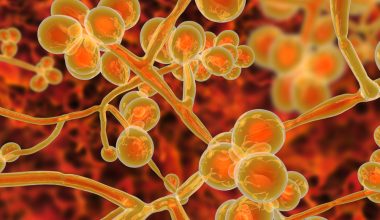

Ο καρκίνος του παχέος εντέρου εκδηλώνεται στο κατώτερο τμήμα του πεπτικού σας συστήματος. Είναι ελάχιστα ξεχωριστός από τον καρκίνο του ορθού (ο καρκίνος που αναπτύσσεται πολύ κοντά στον πρωκτό) αλλά συνήθως αναφέρονται και οι δύο ως “καρκίνος του παχέος εντέρου”.

Ο καρκίνος του παχέος εντέρου αρχίζει κατά κανόνα ως μικρές, μη-καρκινικές (καλοήθεις) μάζες κυττάρων που ονομάζονται αδενωματώδεις πολύποδες. Με τον καιρό ορισμένοι από αυτούς τους πολύποδες εξελίσσονται σε καρκινικά κύτταρα του παχέος εντέρου.

Οι πολύποδες μπορεί να προκαλέσουν συμπτώματα, τα οποία, ωστόσο είναι πολλές φορές πολύ ήπια και δεν γίνονται εγκαίρως αντιληπτά. Για το λόγο αυτό, οι γιατροί συστήνουν τακτικές εξετάσεις προσυμπτωματικού ελέγχου για την έγκαιρη πρόληψη του καρκίνου του παχέος εντέρου, μέσω του ελέγχου των πολυποδών πριν εξελιχθούν σε καρκίνο του παχέος εντέρου.